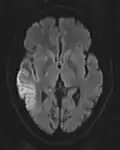

ADC image of the same case of cerebral infarction as seen on DWI in section above

An apparent diffusion coefficient (ADC) image, or an ADC map, is an MRI image that more specifically shows diffusion than conventional DWI, by eliminating the T2 weighting that is otherwise inherent to conventional DWI.[24][25] ADC imaging does so by acquiring multiple conventional DWI images with different amounts of DWI weighting, and the change in signal is proportional to the rate of diffusion. Contrary to DWI images, the standard grayscale of ADC images is to represent a smaller magnitude of diffusion as darker.[23]

Cerebral infarction leads to diffusion restriction, and the difference between images with various DWI weighting will therefore be minor, leading to an ADC image with low signal in the infarcted area.[24] A decreased ADC may be detected minutes after a cerebral infarction.[26] The high signal of infarcted tissue on conventional DWI is a result of its partial T2 weighting.[27]